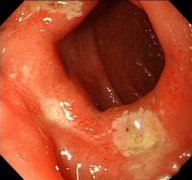

十二指腸炎是指發(fā)生于十二指腸的炎癥,分為原發(fā)性和繼發(fā)性兩種,原發(fā)性者也稱非特異性十二指腸炎。本病臨床癥狀缺乏特征性,主要表現(xiàn)為上腹部疼痛、惡心、嘔吐、嘔血和黑便,有時(shí)和十...